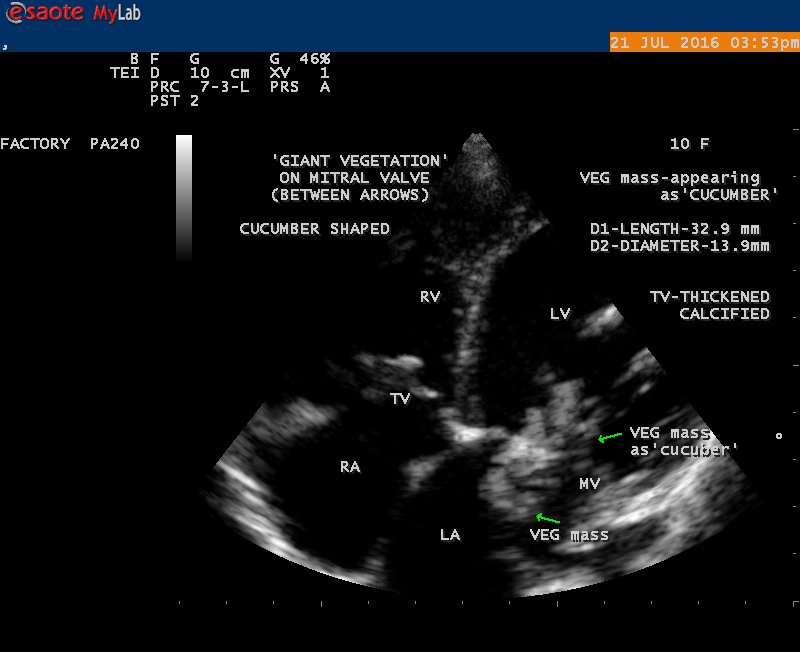

A 10 year female child was referred for echocardiographic evaluation with an apical systolic murmur. The child was having recurrent episodes of rheumatic fever (febrile illness with joint pains) at the age of 5-6 years and taken some treatment from the local medical practitioner, but she was not taken penicillin prophylaxis earlier. The child was remained afebrile for long period and no precipitating factors of infective endocarditis such as dental or genitourinary procedures in the past. General examination revealed normal growth and development, no cyanosis and clubbing and peripheral signs of infective endocarditis such s Osler’s nodes, Janeway lesions, Roths spots and splinter haemorrhages are not present and they are relatively rare in children. Physical examination revealed a grade 3/6 , blowing, high pitched, holosystolic murmur with a constant intensity and duration on dynamic auscultation and loudest at the apex with a radiation to left axilla and transmitted to the left infrascapular area and vertebral coloumn and it is due to the flow generating the murmur is directed posterolaterally within the left atrial cavity, suggesting the murmur of mitral regurgitation due to the rupture of chordae tendineae of anterior mitral leaflet. Blood culture revealed normal. Blood chemistry revealed the positive serum ASO titer, suggesting a recent streptococcal infection and other parameters are normal. X- ray chest reveled moderate cardiomegaly and ECG revealed a left ventricular volume overload pattern of eccentric hypertrophy due to LV dilatation as a result of severe mitral regurgitation and a normal rhythm. Transthoracic echocardiography revealed a giant vegetation ‘popcorn’ like in Figures 1,3 and 4 and ‘cucumber’ like in Figure 2, mainly attached to base and apical portion of anterior mitral leaflet as shown in Figure 31 and manifested in various size and shapes as shown in Figures 1 to 33. A flail anterior leaflet with a disorganized mitral regurgitation jet as shown in Figure 16 and 21 and the posterior leaflet is embedded with vegetation and resulting in ‘kissing forms’ as shown in Figures 13, 14 and 15 in echocardiography imaging. Tricuspid valve is also thickened and calcified as shown in Figure 2 in addition to thickened and calcified mitral leaflets, suggesting an underlying rheumatic etiology predisposing to the formation of vegetation. The child was given 1.2 million units of intramuscular benzathine penicillin injection as a therapeutic and initial prophylaxis dose for rheumatic fever and advised every 3 weeks for life long. Small doses of digoxin and diuretics are also prescribed and advised early surgery (mitral valve replacement) Transthoracic 2D images are as in Figures 1 to 33 are given below

The most common and direct evidence of infective endocarditis is the vegetation and it begins as a microscopic focus of infection and gradually grows into a conspicuous mass. It is typically an irregularly shaped, highly mobile, echogenic mass attached to the free edge of a valve leaflet ( most commonly at the coaptation line) and tends to develop on the ‘upstream’ side of the valve leaflets ( ie, the ventricular side of aortic valve and the atrial side of mitral and tricuspid valves. They may be seesile or pedunculated, but usually has an oscillating or fluttering motion, a typical feature of most vegetations. Vegetation move with the leaflet in a more chaotic (‘oscillating’) manner and it may prolapse through the valve into the LV (left ventricle) as it opens as shown in Figures 3, 4 and 16 and into LA (left atrium) as it closing (Figure 5 and 6) . The mass of vegetation is typically homogeneous with echogenicity similar to that of the myocardium. The infectious process often alter the valvular structure and function. Extensive involvement of the leaflet may result in chordal rupture, leading to severe regurgitation as shown in Figure 21 . Direct and typical signs of RMCT (ruptured mitral chordate tendineae) were chain-flail or whiplash-like changes and had an incidence of 86.7%, causing severe regurgitation and mitral chordal rupture is the leading cause of flail mitral leaflet[30]. A large vegetation may obstruct the valve orifice as shown in Figure 1 and 2 , sometimes termed as “obstructive-type bacterial endocarditis” and producing a functional valve stenosis ( Ping-Pong mitral stenosis [31]) similar to left atrial myxoma as shown in Figure 29.

The size and shape of vegetation vary due to curling of vegetation. The size of vegetation in this child is 35.6 x 9.3 mm as in Figure 17 , 20 x 23.7 mm as in Figure 1 , 32.9 x 13.9 mm as in Figure 2 .

The shape of vegetation varies in this child as ‘popcorn’ like (Figures 1,3 and 4 ), rod-shaped (Figure ), basket shaped (Figure 7 )[33-Figure 13.3], ‘baby in hand’ appearance (Figure 18), ‘cucumber shaped (Figure 2 ) and a ‘bunch of plantain’appearance (Figure 33 ), ring shaped (Figure 19 }, bileaflet structure (Figure 9 )with bileaflet MR jet as shown in Figure 10 . and kissing forms (Figure 13 - parasternal long axis view, Figure 14 - apical four chamber view and Figure 15 - short axis view)